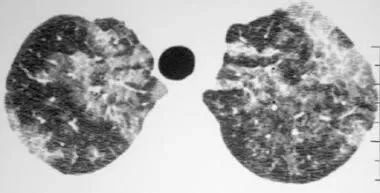

到医院检查,医生听诊发现双肺有湿啰音,胸部CT提示双肺有大片磨玻璃影,呈“蝴蝶形”分布。进一步支气管肺泡灌洗后抽出的是“乳白色”的灌洗液,最终确诊为一种罕见的肺部疾病——肺泡蛋白沉积症。

肺CT表现

影像学检查中,胸部X线常提示双肺对称性浸润阴影。高分辨率CT(HRCT)具有特征性表现,包括:

-

地图征:磨玻璃影中夹杂正常或轻度病变区域,呈地图样分布;

铺路石征:磨玻璃影合并小叶间隔增厚,呈多边形排列;

支气管充气征:病灶区仍可见气体充盈支气管。